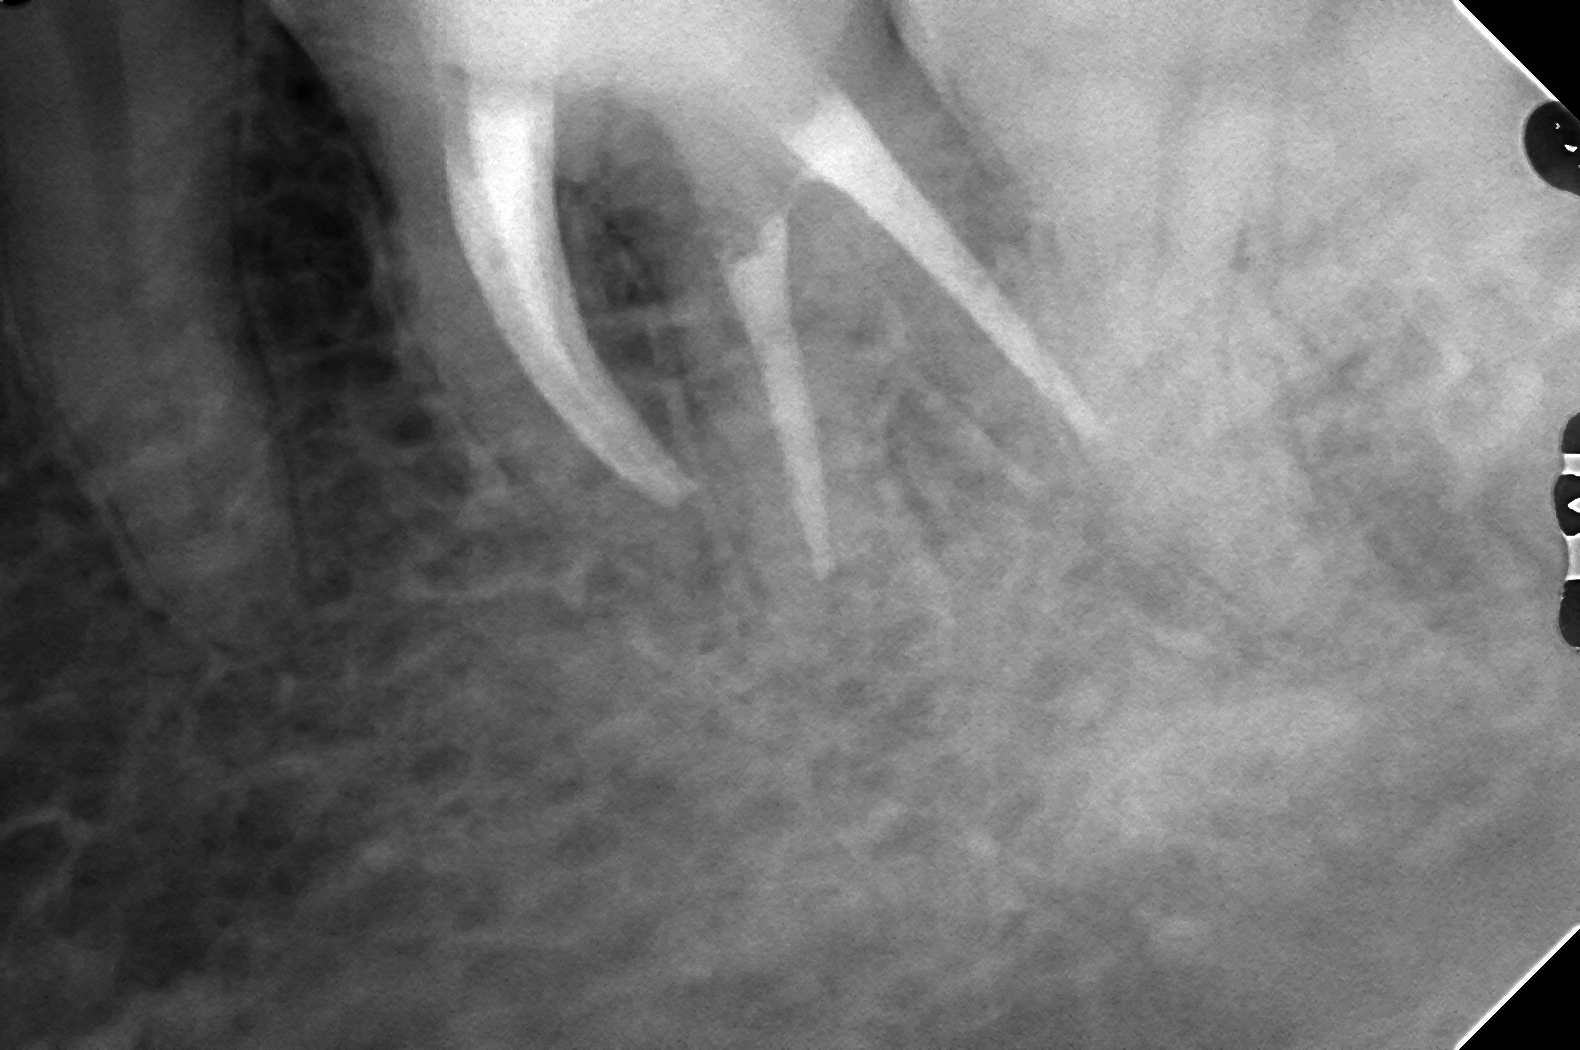

左が正方線、右が近心投影

遠心舌側根が未処置であることがわかります。

近心は2本入ってます

近心の湾曲がきつく、NTファイルがないともっと過剰切削になっていましたね

遠心舌側根の治療ができていますね

近心根も2根ともきれいに形成できていそうですね